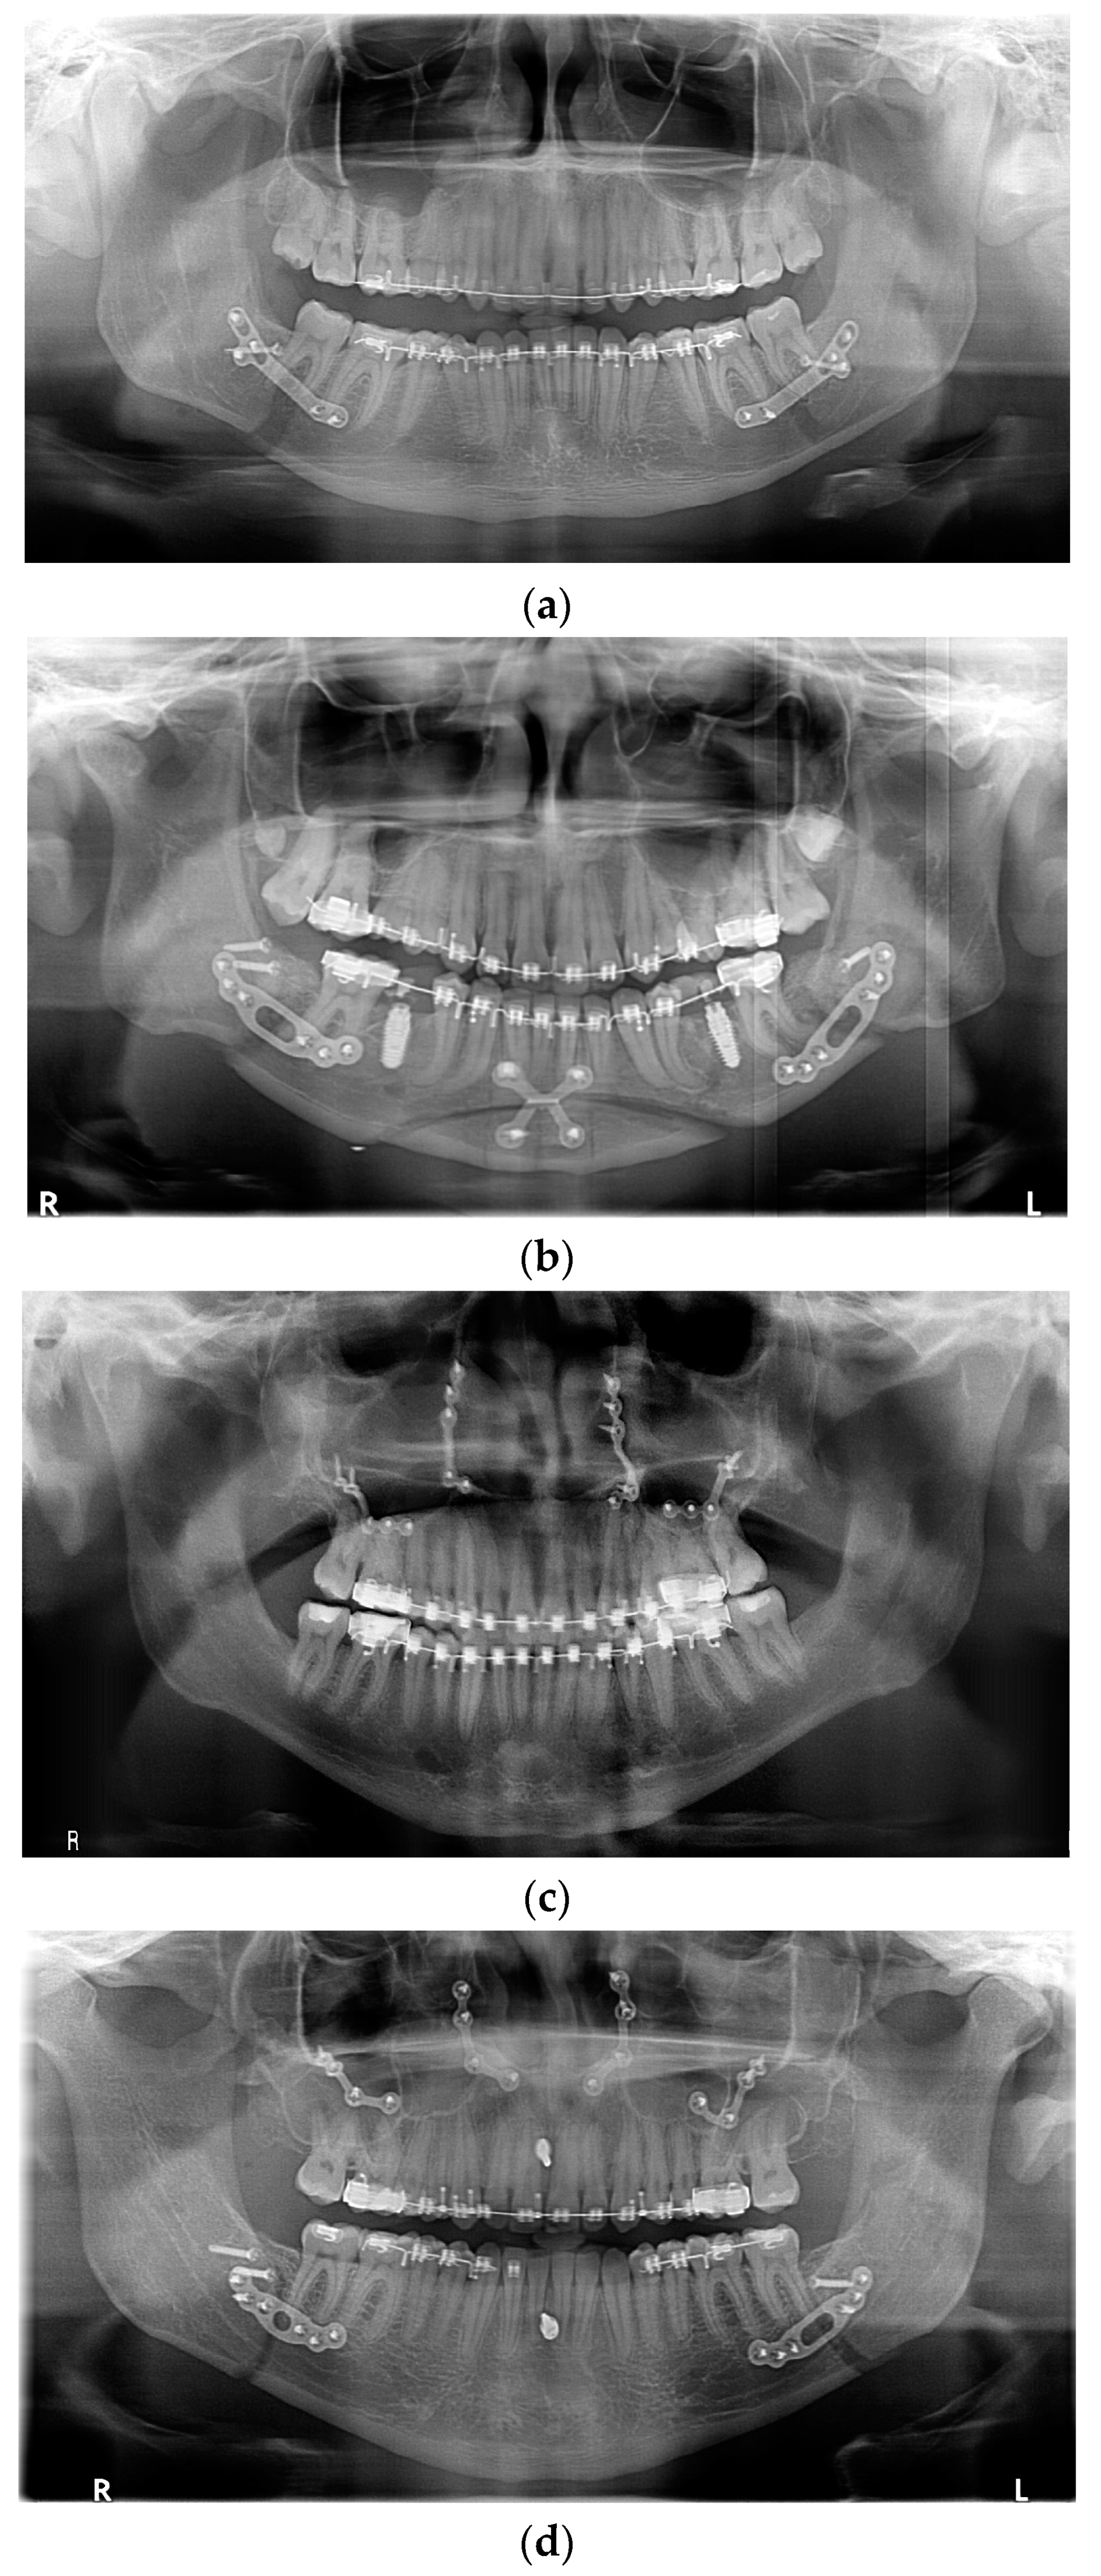

All fixation hardware used in orthognathic procedures was made of titanium (Figure 1).

Figure 1.

Panoramic X-ray with fixation hardware: (a) after BSSO; (b) after BSSO and genioplasty; (c) after Le Fort I osteotomy; (d) after bimax; (e) after bimax with maxillary segmentation and genioplasty.